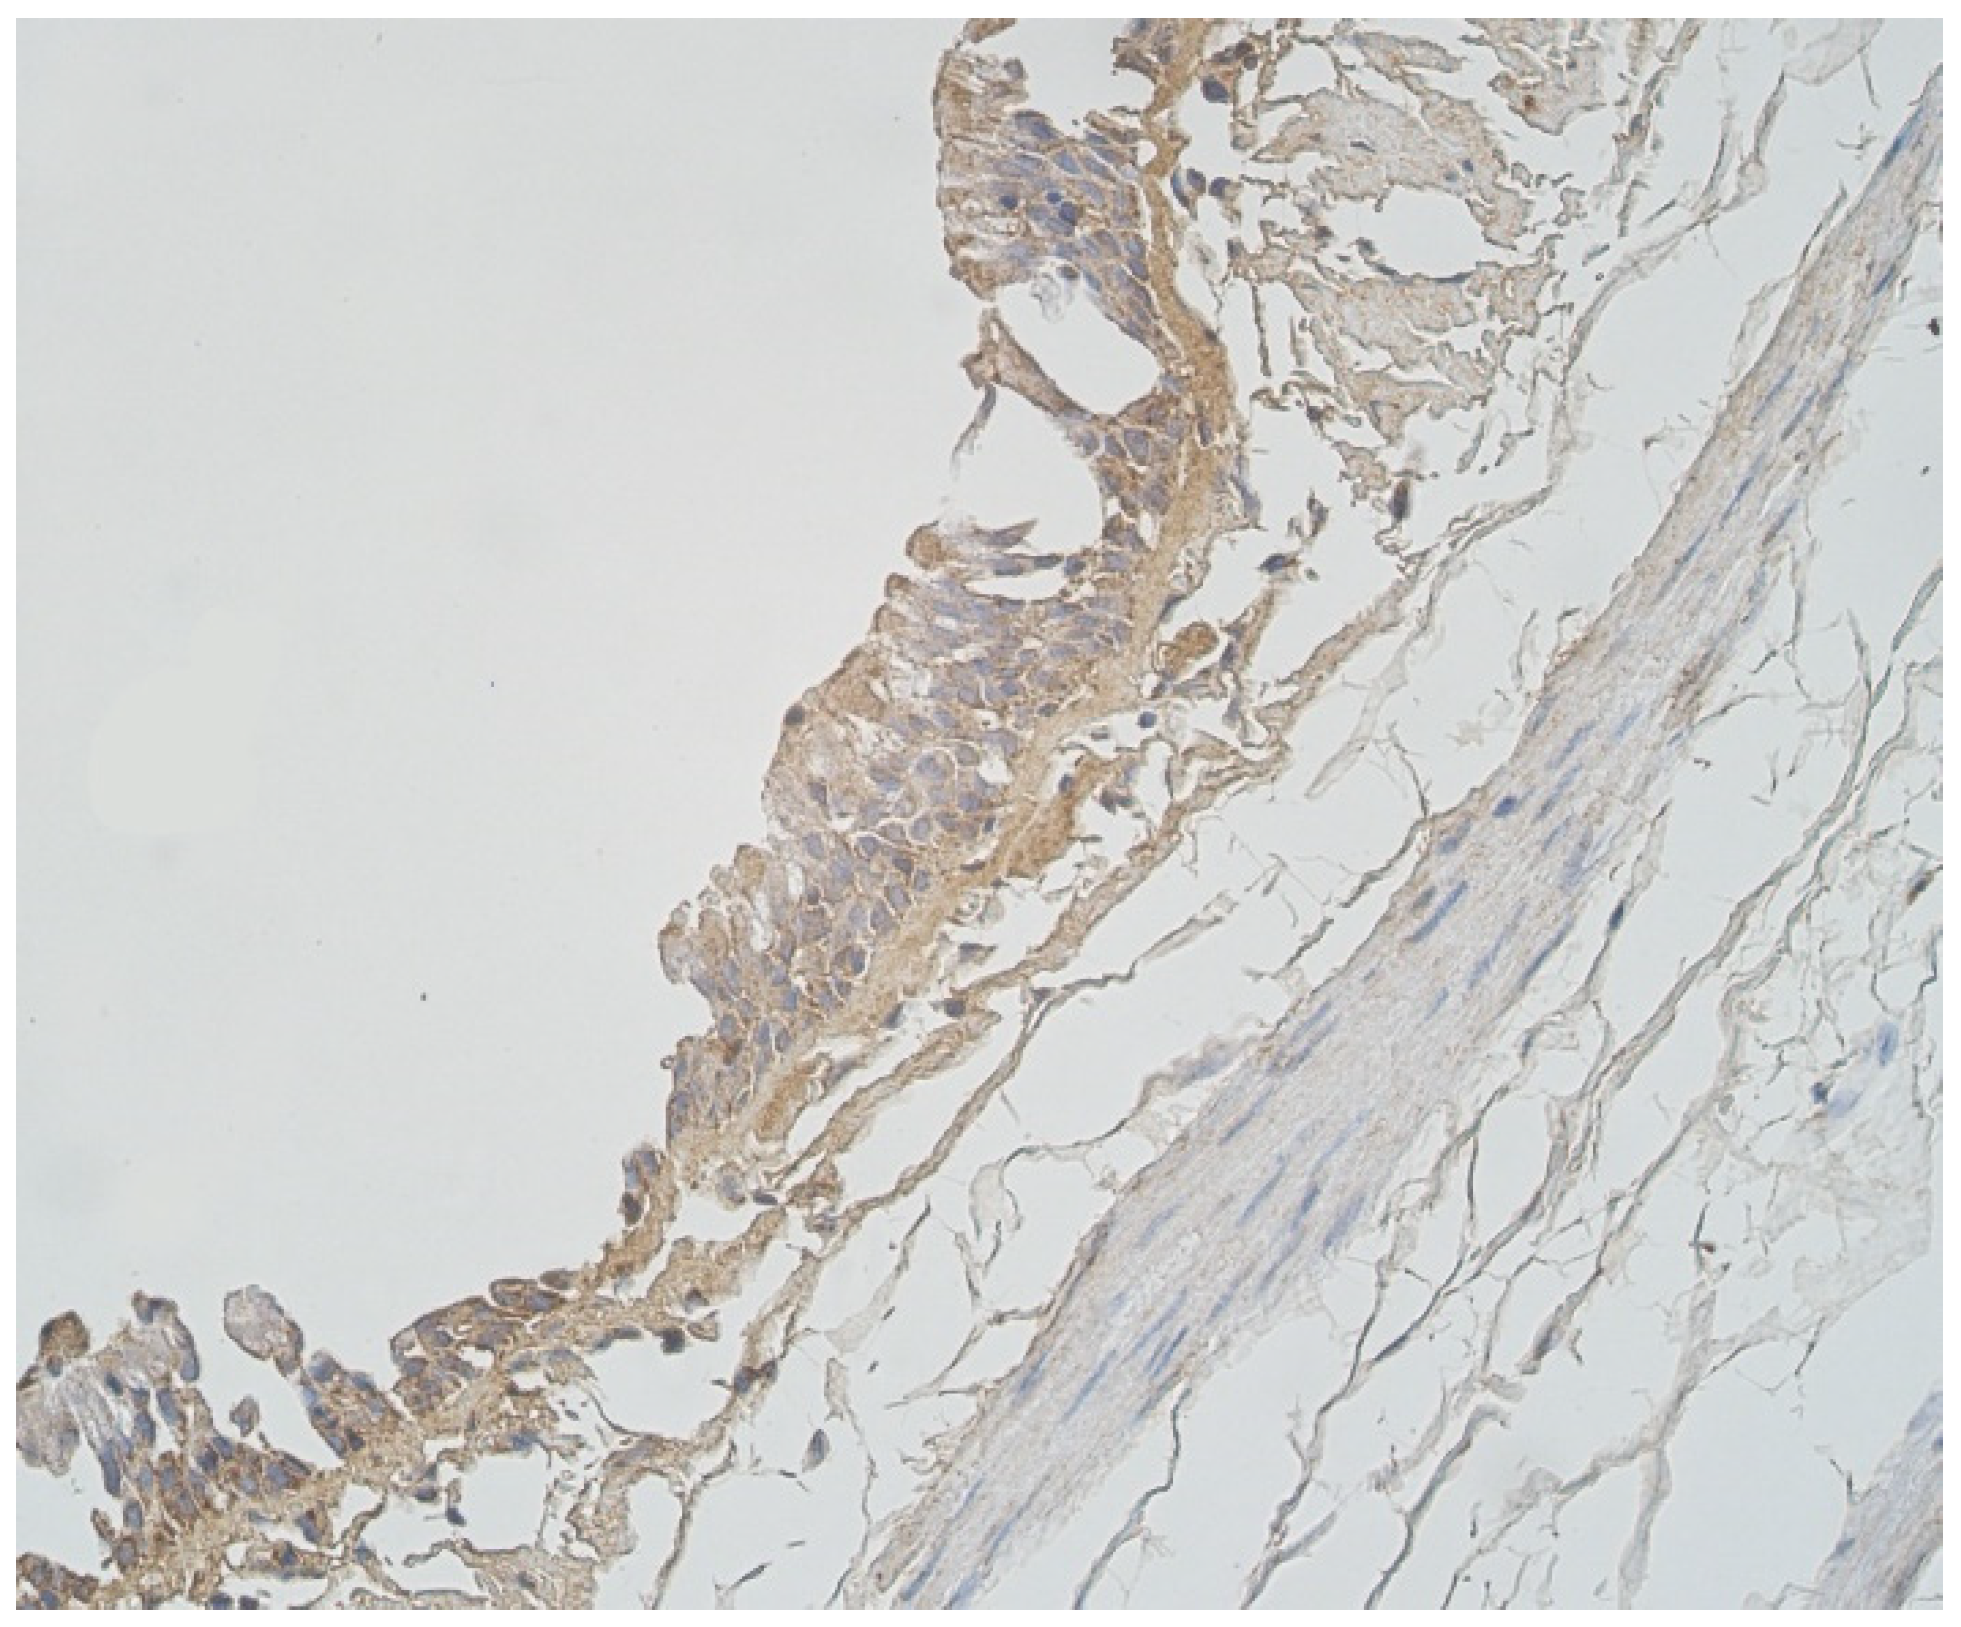

3.2. Immunohistochemical (IMH) Data